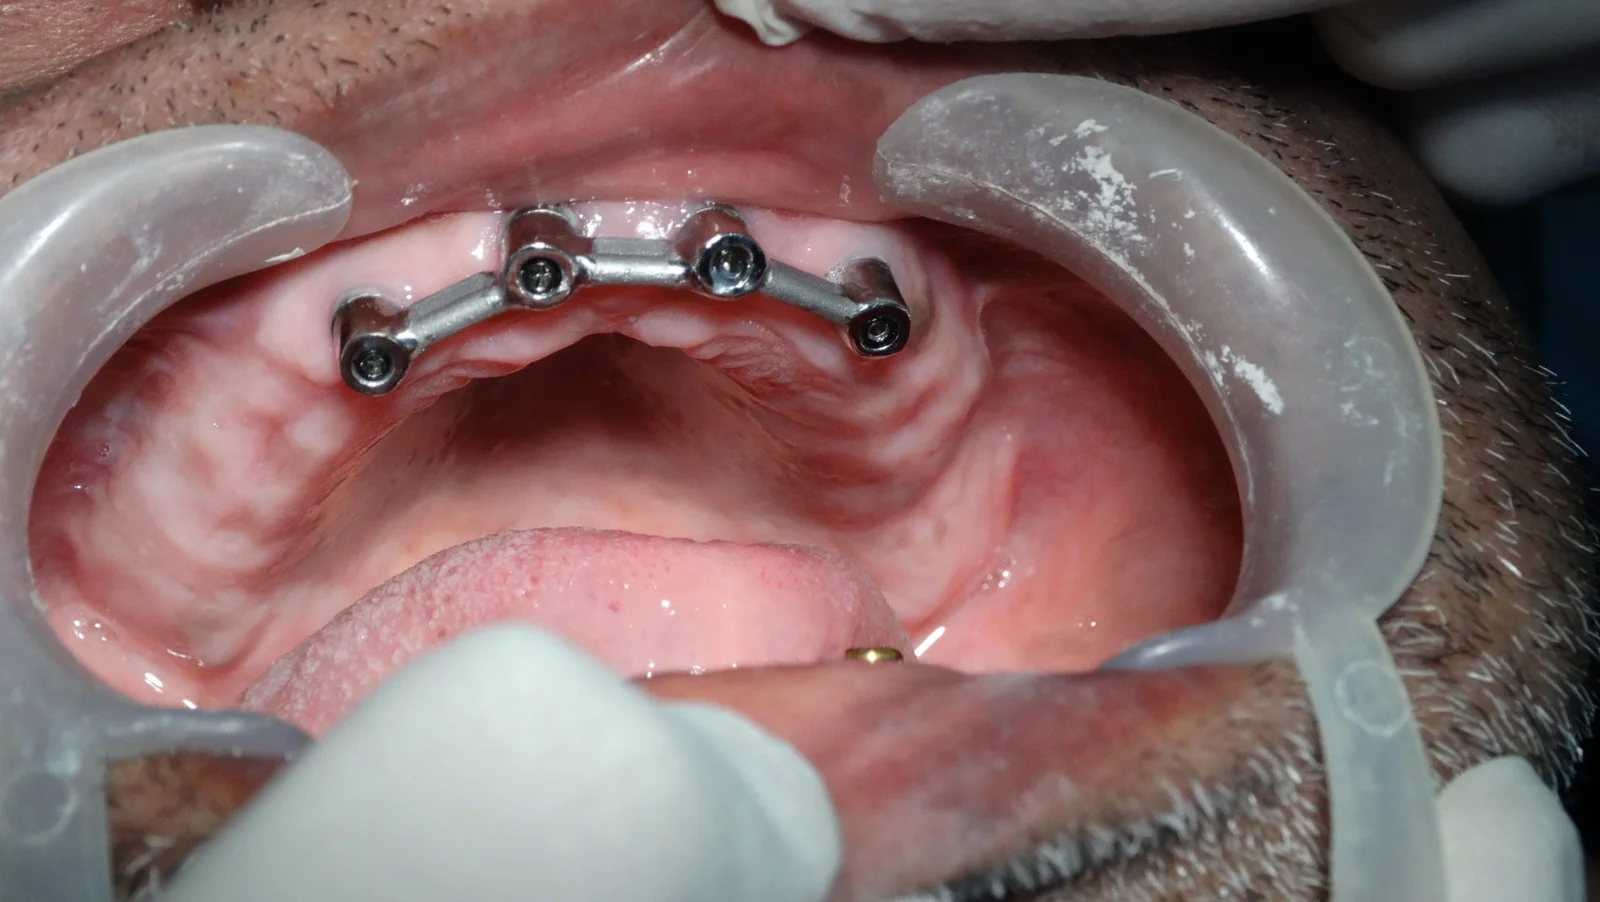

Implant Supported Removable Dentures

These dentures are retained or snapped upon the dental implants but can be removed by the patient. The benefit of these dentures are the stability and retention, offering far more efficient chewing than conventional bone-supported dentures.

As a Prosthodontist, Dr. Neha Bagrecha ensures that even when bone is excessively resorbed, putting dental implants preserves the jaw bone and gives a comfortable prosthesis.

Removable Dentures Case Progression